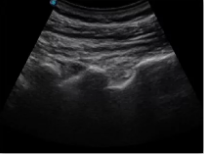

不同的探頭對應(yīng)于不同的臨床領(lǐng)域,不同的探頭頻率也應(yīng)用于不同的人體組織。超聲波在人體中的衰減與探頭頻率有關(guān),探頭頻率越高,穿透力越弱,分辨率越高,而探頭頻率越低,穿透力越強(qiáng),分辨率越低。因此在檢查淺表器官時應(yīng)選用高頻探頭,而檢查深部臟器時則選用穿透性強(qiáng)的低頻探頭。